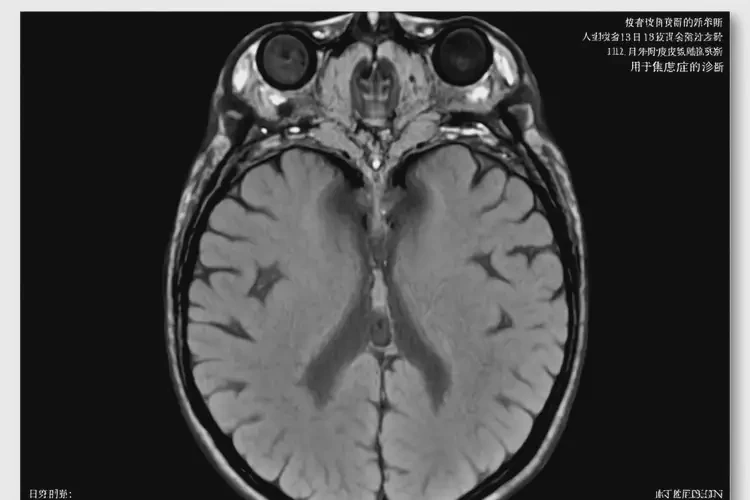

3. 影像学检查:如MRI、CT等,用于更详细地了解大脑结构和功能,费用一般在500-1000元之间。

重庆去医院检查轻度焦虑贵不贵(图2)